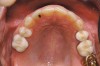

Figure 5a  A 22-year-old female presented, concerned about smile, overbite, and baby tooth. Facial views reveal excellent skeletal components with excessive gingival display and insufficient lip support. Anterior deep bite with extruded and retruded anterior dentition secondary to unstable relationship.

Figure 5b  A 22-year-old female presented, concerned about smile, overbite, and baby tooth. Facial views reveal excellent skeletal components with excessive gingival display and insufficient lip support (A and B). Anterior deep bite with extruded and retruded anterior dentition secondary to unstable relationship.

Figure 5c  Note lack of alveolar development from congenitally missing Nos. 24 and 25. Surgical procedures after 5 months of orthodontic alignment included single-tooth osteotomies Nos. 6 to 11 and Nos. 21 to 28 and buccal corticotomies on all other teeth. Anchorage plate was stabilized to piriform rim.

Figure 5c

Figure 5d  Note lack of alveolar development from congenitally missing Nos. 24 and 25. Surgical procedures after 5 months of orthodontic alignment included single-tooth osteotomies Nos. 6 to 11 and Nos. 21 to 28 and buccal corticotomies on all other teeth. Anchorage plate was stabilized to piriform rim.

Figure 5d

Figure 5e  Anchorage plate was stabilized to piriform rim (E through H). Final result 12 months postsurgery (F). There is significant lateral dentoalveolar expansion of arches and alveoloskeletal correction in maxillary and mandibular anterior regions. Alveolar bone volume was increased in lower anterior to create optimal implant sites and establish ideal interincisal function and stability.

Figure 5e